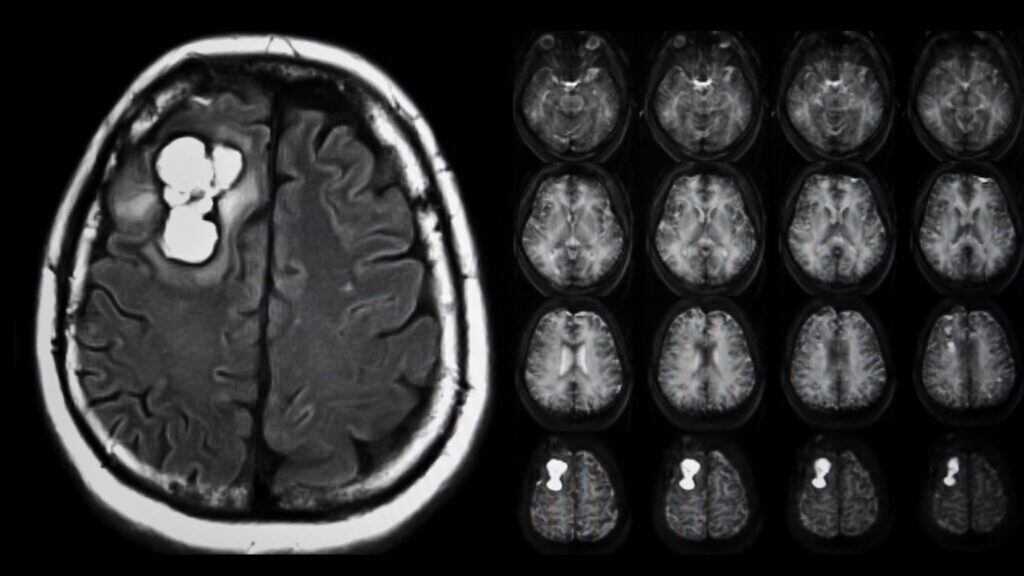

Diferentemente das abordagens tradicionais, que tratam o tumor como um bloco homogêneo, o novo método analisa milhares de células individualmente. Isso é possível graças ao sequenciamento de células únicas, tecnologia que permite mapear a atividade genética célula por célula dentro do tumor.

A partir dessa base, os cientistas criaram um software avançado capaz de cruzar dados de expressão gênica com respostas farmacológicas. Na prática, isso revela quais células são sensíveis ou resistentes a determinados medicamentos, algo essencial para enfrentar a heterogeneidade do glioblastoma.